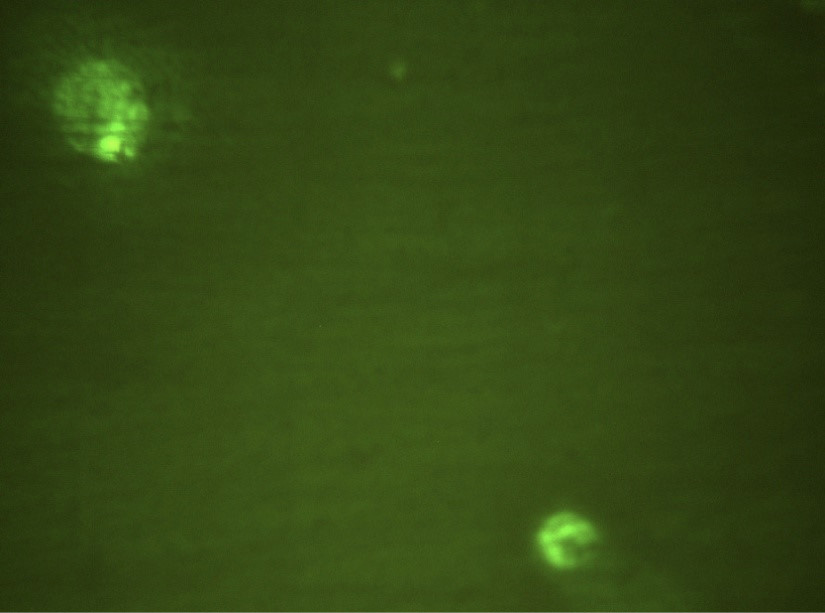

На рис. 1 в поле зрения люминесцентного микроскопа зафиксированы 2 клетки, экспрессирующие CD282 (TLR2), меченные FITC. Видны ярко окрашенные скопления в виде гранул. На рис. 2 в фазовом контрасте видны 4 клетки, выделенные из экссудата пародонтального кармана. На рис. 3 при люминисцентном микроскопировании представлены эти же 4 клетки с неярким диффузным окрашиванием CD284-FITC (TLR4). Таким образом, в результате данного пилотного исследования выявлена и визуализирована экспрессия рецепторов врождённого иммунитета TLR2 и TLR4 в десневой жидкости и экссудате пародонтального кармана при ХП.

Рис. 1. Клетки десневой жидкости, экспрессирующие CD282. Окраска FITC, ×1000.

Рис. 3. Клетки десневой жидкости, экспрессирующие CD284. Окраска FITC, ×1000.